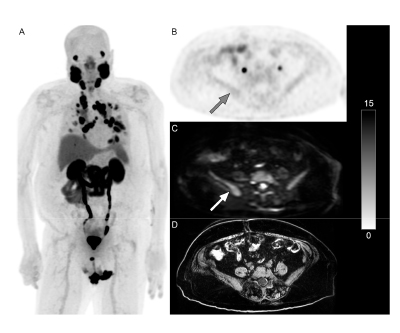

Whole-Body Diffusion-Weighted Imaging Spots PSMA-negative Lesions

Adding whole-body diffusion-weighted imaging (WB DWI) to PSMA PET scans for patients with metastatic castration-resistant prostate cancer can allow radiologists to identify PSMA-negative lesions, potentially altering their treatment plan. The most common locations for these lesions were the lymph nodes followed by bones and, less frequently, the lungs and liver.

This research was published in the Journal of Clinical Medicine in March 2025.